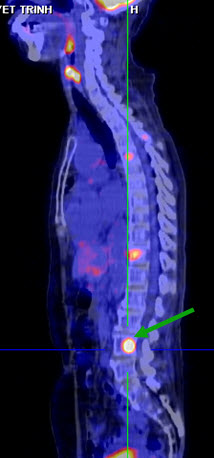

Hình 6. Bệnh nhân Lê T. H. G., nữ, 41 tuổi. Chẩn đoán: Ung thư vú đã điều trị cách đấy 8 năm. Hiện tại bệnh nhân đi khám lại thấy có chỉ điểm ung thư (CA 15-3) tăng. Trên hình PET/CT cho thấy tổn thương xương nhiều ổ tại cột sống, xương cánh tay (các mũi tên). (Nguồn: Mai Trọng Khoa – Trung tâm Y học hạt nhân và ung bướu – BV Bạch Mai)